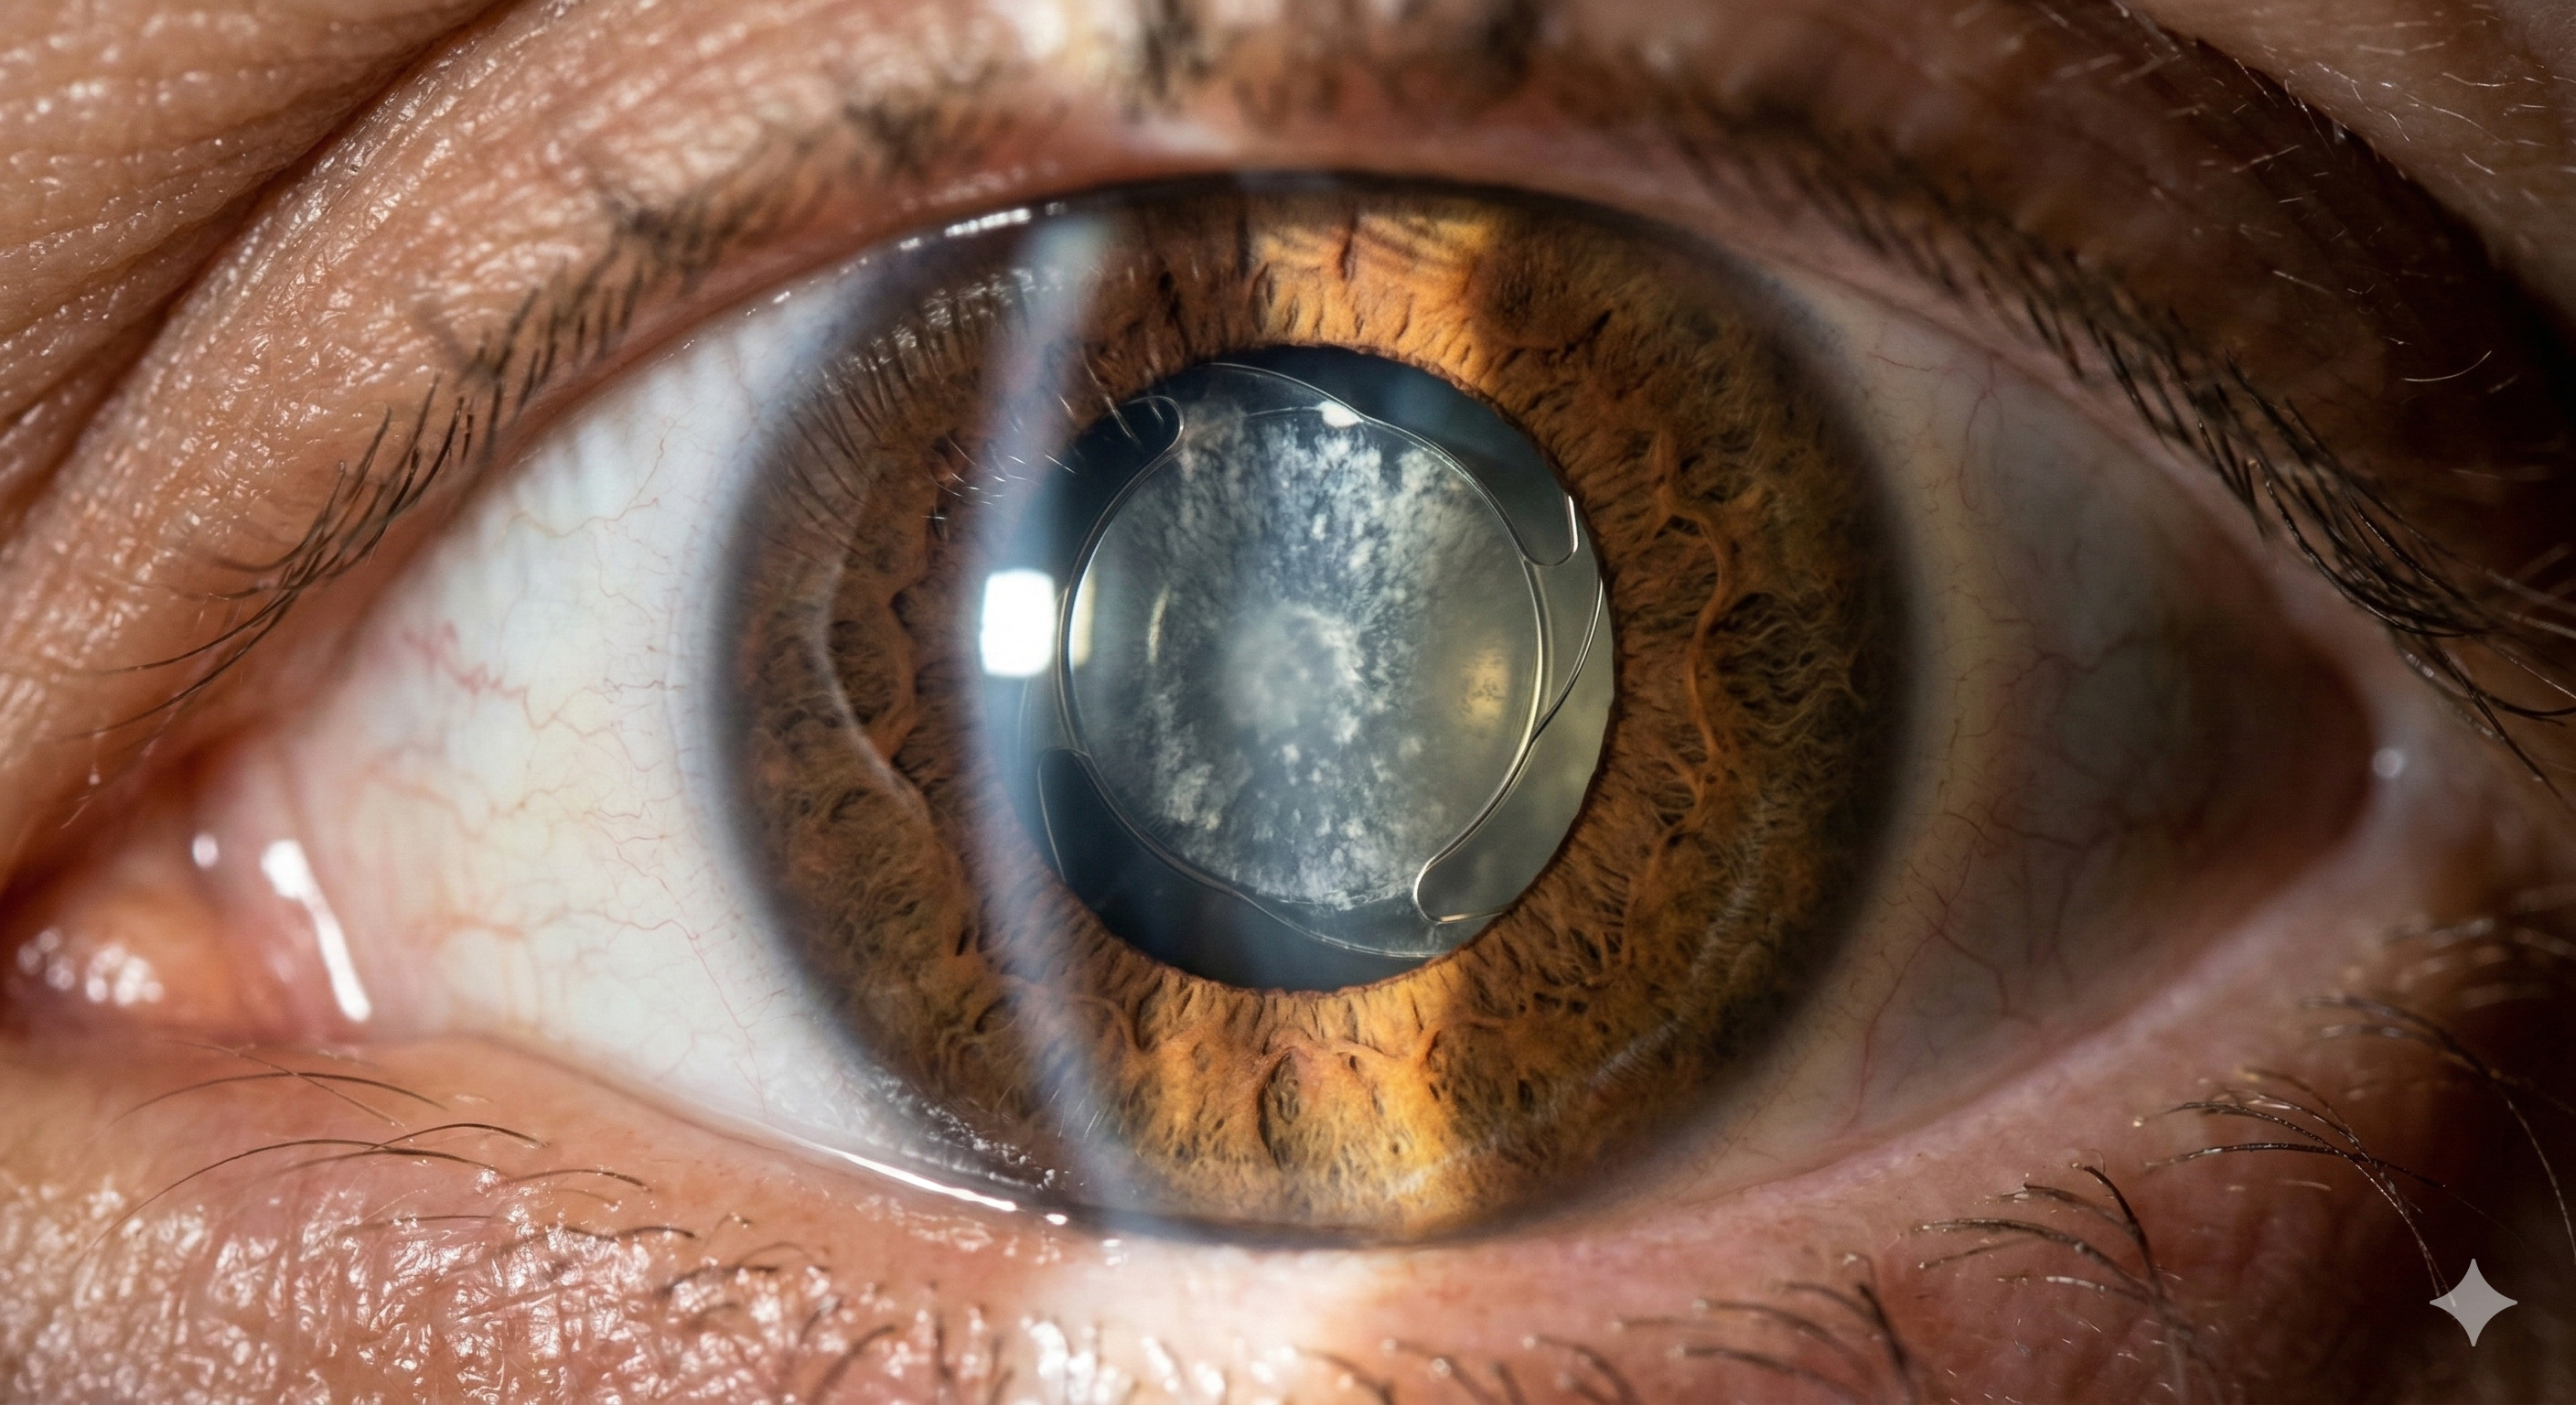

Comúnmente llamada 'limpieza de lente', es una nubosidad que se forma detrás del lente intraocular meses o años después de la cirugía.